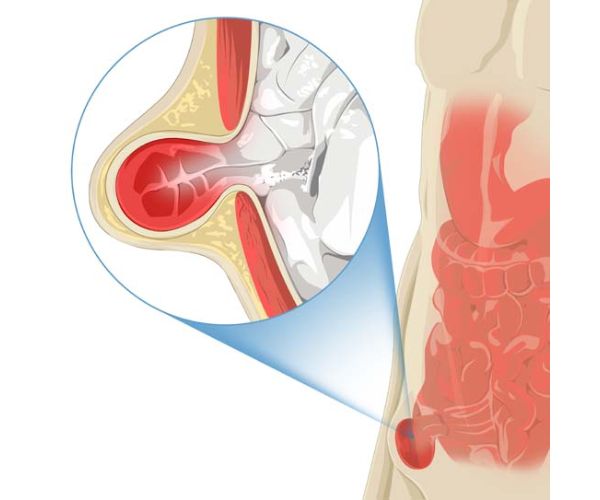

ما هي مضاعفات عملية الفتق الإربي؟

رغم أن عملية الفتق الإربي تُصنّف ضمن العمليات الآمنة والروتينية، إلا أن هناك احتمالية لظهور بعض المضاعفات، لكنها نادرة الحدوث وتختلف من شخص لآخر حسب الحالة الصحية ومدى التزام المريض بتعليمات الطبيب بعد الجراحة.

فيما يلي أبرز المضاعفات المحتملة التي يجب معرفتها:

- العدوى في موضع العملية: قد تظهر على شكل احمرار شديد، تورم، ألم متزايد، أو خروج إفرازات من الجرح، وفي هذه الحالة يحتاج المريض لعلاج فوري بالمضادات الحيوية.

- حدوث نزيف في منطقة الجرح: وهو أمر نادر، لكنه قد يحدث ويتطلب مراقبة مستمرة للتأكد من توقف النزيف والسيطرة عليه.

- إصابة الأعضاء المجاورة أو الأوعية الدموية: خلال العملية قد تتأثر بعض الأنسجة المحيطة، خاصة في الحالات المعقدة أو عند وجود التصاقات قديمة.

- احتباس البول: وهو عرض مؤقت قد يعاني منه بعض المرضى بعد العملية، وفي بعض الحالات يُلجأ إلى استخدام قسطرة بولية لتصريف البول حتى تستعيد المثانة وظيفتها الطبيعية.

- الألم المزمن في منطقة الفخذ: في حالات قليلة، قد يستمر الألم لفترة طويلة بعد العملية بسبب تهيج الأعصاب أو تفاعل الجسم مع الشبكة الصناعية التي تُزرع لتقوية جدار البطن.

- مضاعفات مرتبطة بالتخدير: بعض المرضى قد يعانون من رد فعل تجاه التخدير مثل الغثيان، الدوخة، أو اضطرابات مؤقتة في الوعي، وغالبًا ما تزول هذه الأعراض سريعًا.

رغم ندرة هذه المضاعفات، إلا أن المتابعة الطبية الدقيقة والالتزام بالتعليمات يقللان بشكل كبير من فرص حدوثها، ويضمنان للمريض تعافيًا أسرع وأكثر أمانًا.